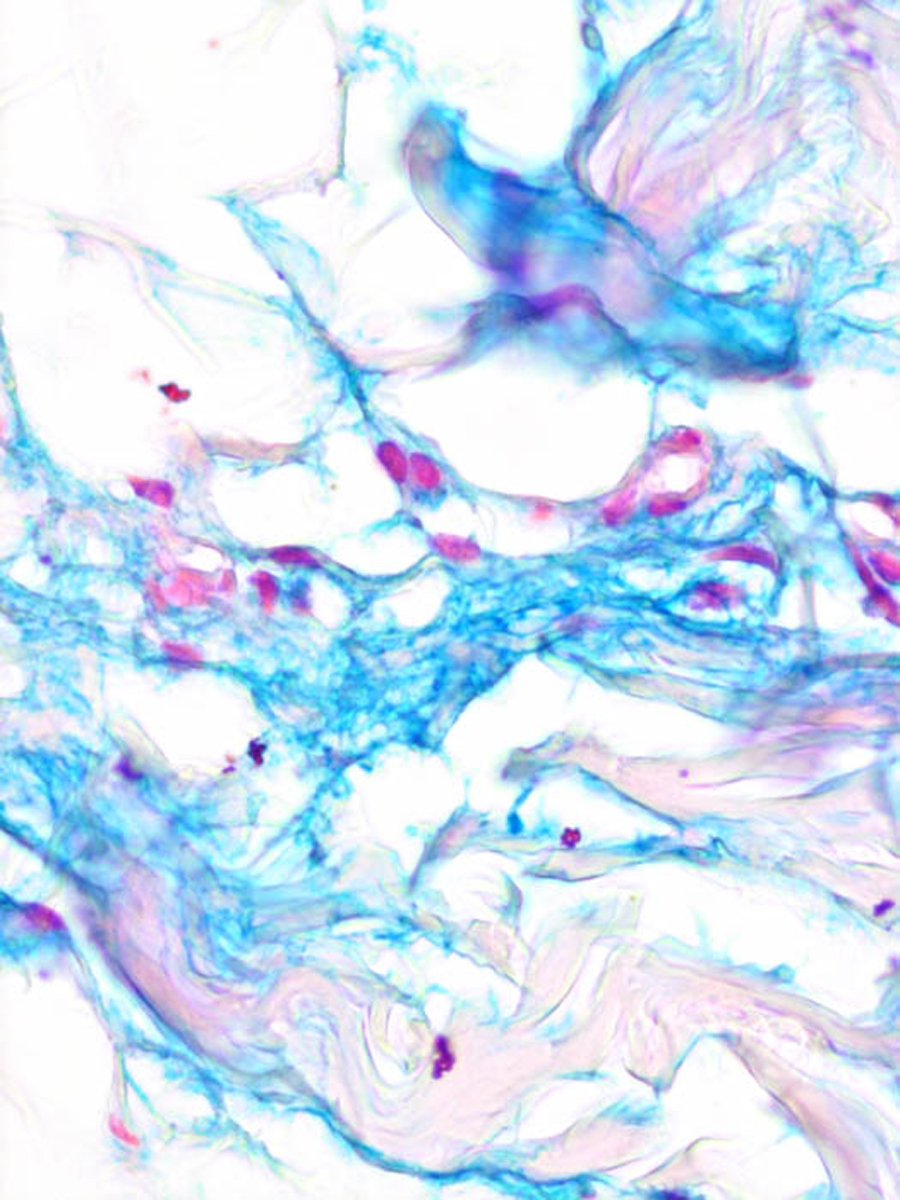

In many instances, especially in early cases, histochemical staining reveals the presence of hyaluronic acid between the bundles of collagen, particularly in the areas of fenestration. Staining with toluidine blue usually reveals metachromasia, which is most evident at pH 7.0, weaker at pH 5.0, and absent at pH 1.5, indicating the presence of only nonsulfated acid mucopolysaccharides . Although the hyaluronic acid is usually present throughout the dermis, it may be present only in the deeper portion of the dermis .

|

In some instances, staining with toluidine blue at pH 7.0 is more intense if unfixed cryostat sections are used in place offormalin-fixed material . In some cases, even frozen sections have failed to stain with Alcian blue or toluidine blue . It may be postulated that in long-standing cases in which the disease has reached a steady stage of collagen turnover, staining for hyaluronic acid may give negative results . In cases of scleredema in which formaldehyde-fixed specimens fail to show acid mucopolysaccharides, they may show them on fixation in 0.05% cetylpyridinium chloride solution and staining with Alcian blue at pH 2.5 . It has been stated that fixation with 1 % cetylpyridinium chloride solution in standard formalin fixative combined with colloidal iron staining gives the best results .